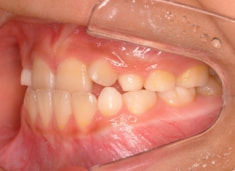

小児期ケース:反対咬合+上顎両側3番埋伏歯

(受け口+3番目の永久歯が左右両方とも埋まってしまい、はえてこない)

治療法:上顎急速拡大装置+クリアスナップ+フェイスマスク+上顎3番は開窓牽引CT写真にて位置確認

治療開始時